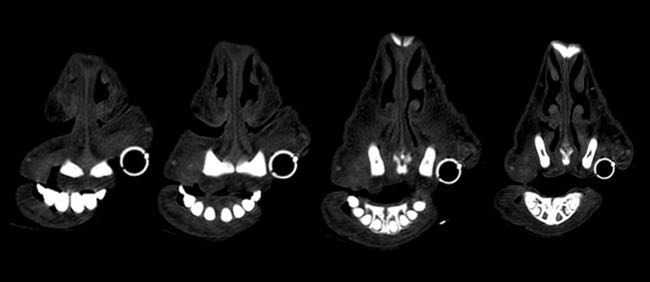

Given the clinical findings and prior experience with upper airway disease, ancillary tests were performed. Thermography did not identify consistent focal increases in temperature across the six animals, making common differentials such as chronic proliferative rhinitis (CPR) or enzootic nasal adenocarcinoma (ENA) less likely. Oestrosis had also been ruled out, as previous treatments targeting this condition failed to result in clinical improvement in the affected animals. Computed tomography (CT) of the head revealed increased soft tissue in the rostral nasal cavity, producing variable obstruction of the nasal meatuses in all sheep. On transverse CT images, soft-tissue thickening causing luminal narrowing was confined to the most rostral nasal cavity and decreased progressively on more caudal slices, where the nasal airway regained a wider lumen (Figure 3). This localisation of obstruction at the alar fold level explained the inspiratory dyspnoea and snoring.

Figure 3. (2 images) Serial images obtained from the computed tomography scanner with different filters. Four sequential cuts of two sheep, from rostral (left) to caudal (right), show increased cellularity and almost complete blockage of the airway in the rostral area, which diminished as the images progress caudally.